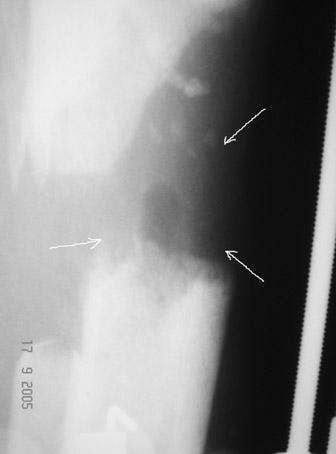

10 дней назад ранка на передней поверхности средней трети голени и по внутренней поверхности нижней трети голени, (по проекции стержня апп.Гофмана) открылись вновь. В настоящий момент отделяемого из обеих ран нет (wound1;2).

Рентгенологически определяется дистракционный регенерат удовлетворительной плотности и наличие в нем полости (now 1;2;3).

После последнего R- снимка 4 дня назад, аппарат переведен в режим фиксации.